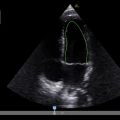

GE Venue è il sistema top di gamma della linea Venue, pensato per il point-of-care.

Con monitor grande da 19″ che facilita la visione da qualsiasi angolo della stanza e supporta esami completi con batteria fino a 4 h, offre imaging clinico chiaro e strumenti automatici basati su intelligenza artificiale per valutazioni rapide e supporto decisionale in ambienti critici, con carrello robusto, gestione intelligente dei cavi e grado di pulizia semplificato per controllo delle infezioni.